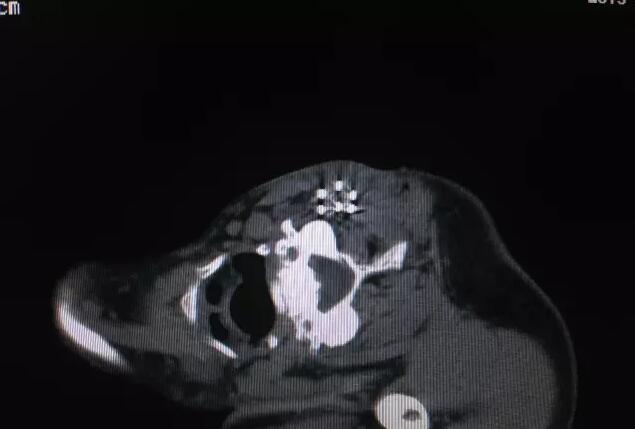

你好我科在省内首先开展CT引导下全身各部位经皮同轴穿刺活检术处于领先地位。已经成功完成肺、纵隔、腹盆腔、腹膜后、脊柱及四肢骨组织等部位穿刺活检1000余例,积累一定经验。活检最小病灶约0.5厘米、活检部位深及纵隔内各组淋巴结,解决了肿瘤病理及基因诊断方面实际问题,使患者更加精准、精细化的个体治疗手段成为可能。另外肿瘤晚期复发及转移瘤粒子植入内放疗,囊肿、脓肿及吻合口瘘穿刺引流术等,也都取得了较好的临床疗效。

你好同轴穿刺技术其原理是在穿刺活检取材装置外面加了一个保护装置,像圆珠笔一样,笔头贴到肿瘤表面,真正取出肿瘤组织的器械是“笔芯”——即活检枪,取材结束后,笔芯退回到圆珠笔壳内,这个外壳就是个保护通道,无需移动,不进入瘤体内,有效避免肿瘤细胞外漏,防止肿瘤种植及针道转移,可起到最大的保护作用。笔芯可多次自由进出针壳,多次、多点取材,取材量大,完全能保证病理及基因诊断。其适应症广,相对禁忌症及绝对禁忌症少;只要是无全身严重心、脑及肺疾病,能耐受相对久卧、静止体位,短时间屏气,常规检查无异常者均可实施。同轴穿刺活检技术可有效减少气胸、出血等常见并发症。